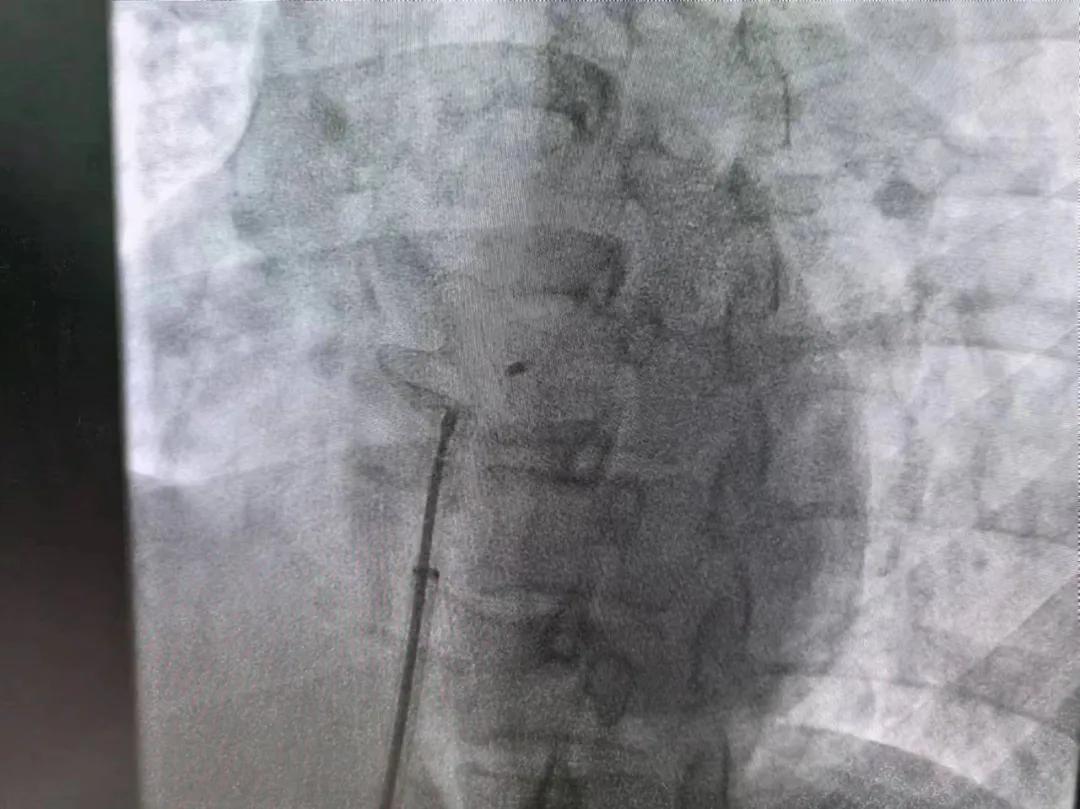

繼3月14日市二院成功開展首例卵圓孔未閉介入封堵術(shù)之后,3月21日上午,市二院院長王瑾及心血管內(nèi)科主任李慧新帶領(lǐng)心血管內(nèi)科介入團隊,再次成功為患者實施“經(jīng)皮房間隔缺損封堵術(shù)”,手術(shù)過程順利。該例病人的成功手術(shù)及康復(fù),標志著市二院心血管內(nèi)科在結(jié)構(gòu)性心臟病介入診療中再次達到了新高度。

患者為中年女性,41歲,近2年一直反復(fù)出現(xiàn)頭暈、頭痛,曾先后在多家醫(yī)院就診。近期患者癥狀加重,出現(xiàn)活動后氣喘合并胸悶癥狀,來到心血管內(nèi)科就診。經(jīng)心臟彩超檢查顯示:患者房間隔下段連續(xù)性中斷,缺損直徑達到了13mm,肺動脈壓已經(jīng)輕度增高,確診為房間隔缺損。

對于房間隔缺損面積較大的患者,如果長時間不注意,不及時介入封堵治療,心功能可能會出現(xiàn)嚴重問題,一旦出現(xiàn)嚴重肺動脈壓高壓及心力衰竭,將喪失診療機會,會嚴重降低患者生活質(zhì)量,且極大縮短患者壽命。

于是,院長王瑾會診后,詳細詢問患者病史,認真分析臨床癥候群并準確診斷,耐心做好患者及家屬病情告知和充分溝通。經(jīng)過完善的術(shù)前評估及準備,心血管內(nèi)科介入團隊成功為患者實施“經(jīng)皮房間隔缺損封堵術(shù)”,手術(shù)過程順利。近日,患者已順利康復(fù)出院。 (尹紅婭 潘長林)